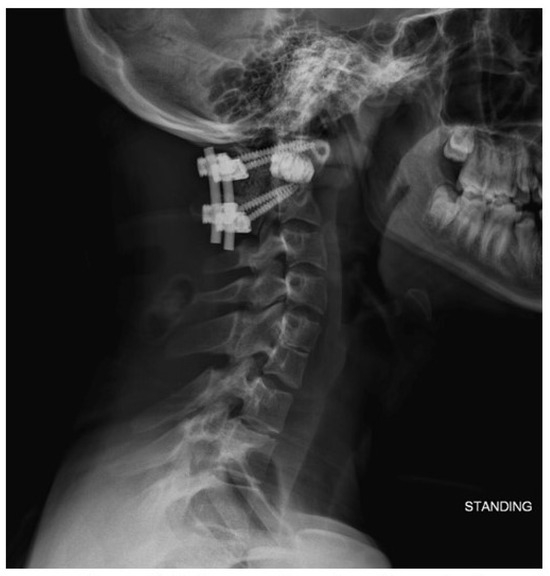

2.2. Imaging and Diagnosis

4. Results